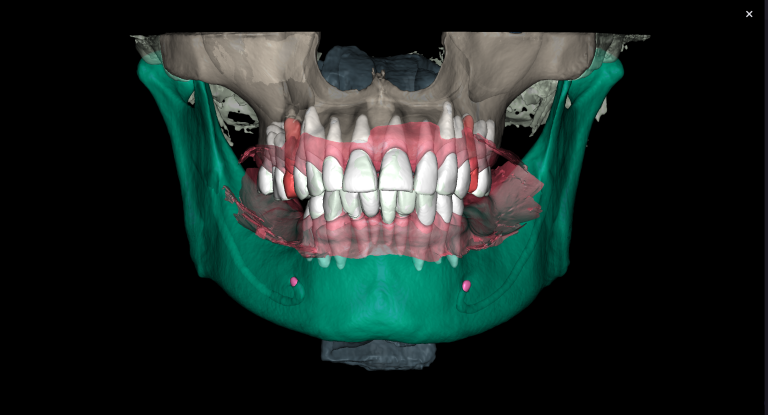

With the help of Diagnocat STL reconstruction, the doctor can visualize changes in the level of bone relative to the roots of the teeth, which are hidden behind the gum.

A cross-sectional radiological report created by Diagnocat AI allows the clinician to detect a subgingival calculus and make an accurate prognosis of each tooth before starting any complex treatment, whilst taking into account all of the endodontic, periodontal and functional criteria.